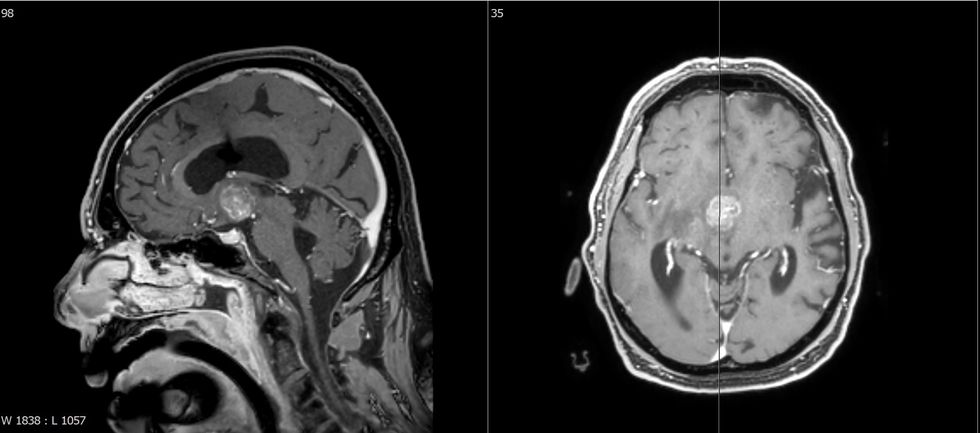

Metastazat e trurit ndodhin në 15-30% të pacientëve me kancer. Tumori primar është kryesisht kanceri i mushkërisë (44%), i gjirit (10%), i veshkës (7%), i traktit gastrointestinal (6%) dhe melanoma (3%).

Trajtimi i metastazave në tru është i mundur duke përdorur modalitete të ndryshme. Koncepti i trajtimit varet nga faktorë të ndryshëm, si lokalizimi, numri, simptomat e shkaktuara dhe gjendja e përgjithshme e pacientit si dhe situata e përgjithshme onkologjike. Në rastin e metastazave simptomatike, qëllimi i operacionit është përmirësimi i gjendjes për të mundësuar terapi të mëtejshme për pacientin edhe nëse ka disa metastaza.